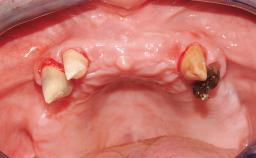

Surgical treatment of a 68-year-old female patient who experienced failure of her conventional bridge in the right maxilla. After removal of the compromised abutment teeth and a healing period of 6 weeks, a sinus floor elevation procedure using the lateral window technique and a composite graft to correct the insufficient bone height is carried out.